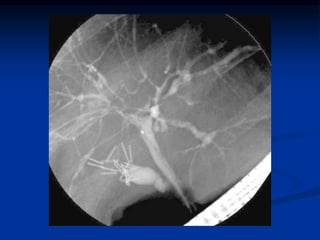

Radiologic features of CD and UC

UC

CD

Feature

Collar button

ulcers

Nodularity

granularity

cobble stoning

string sign of SB